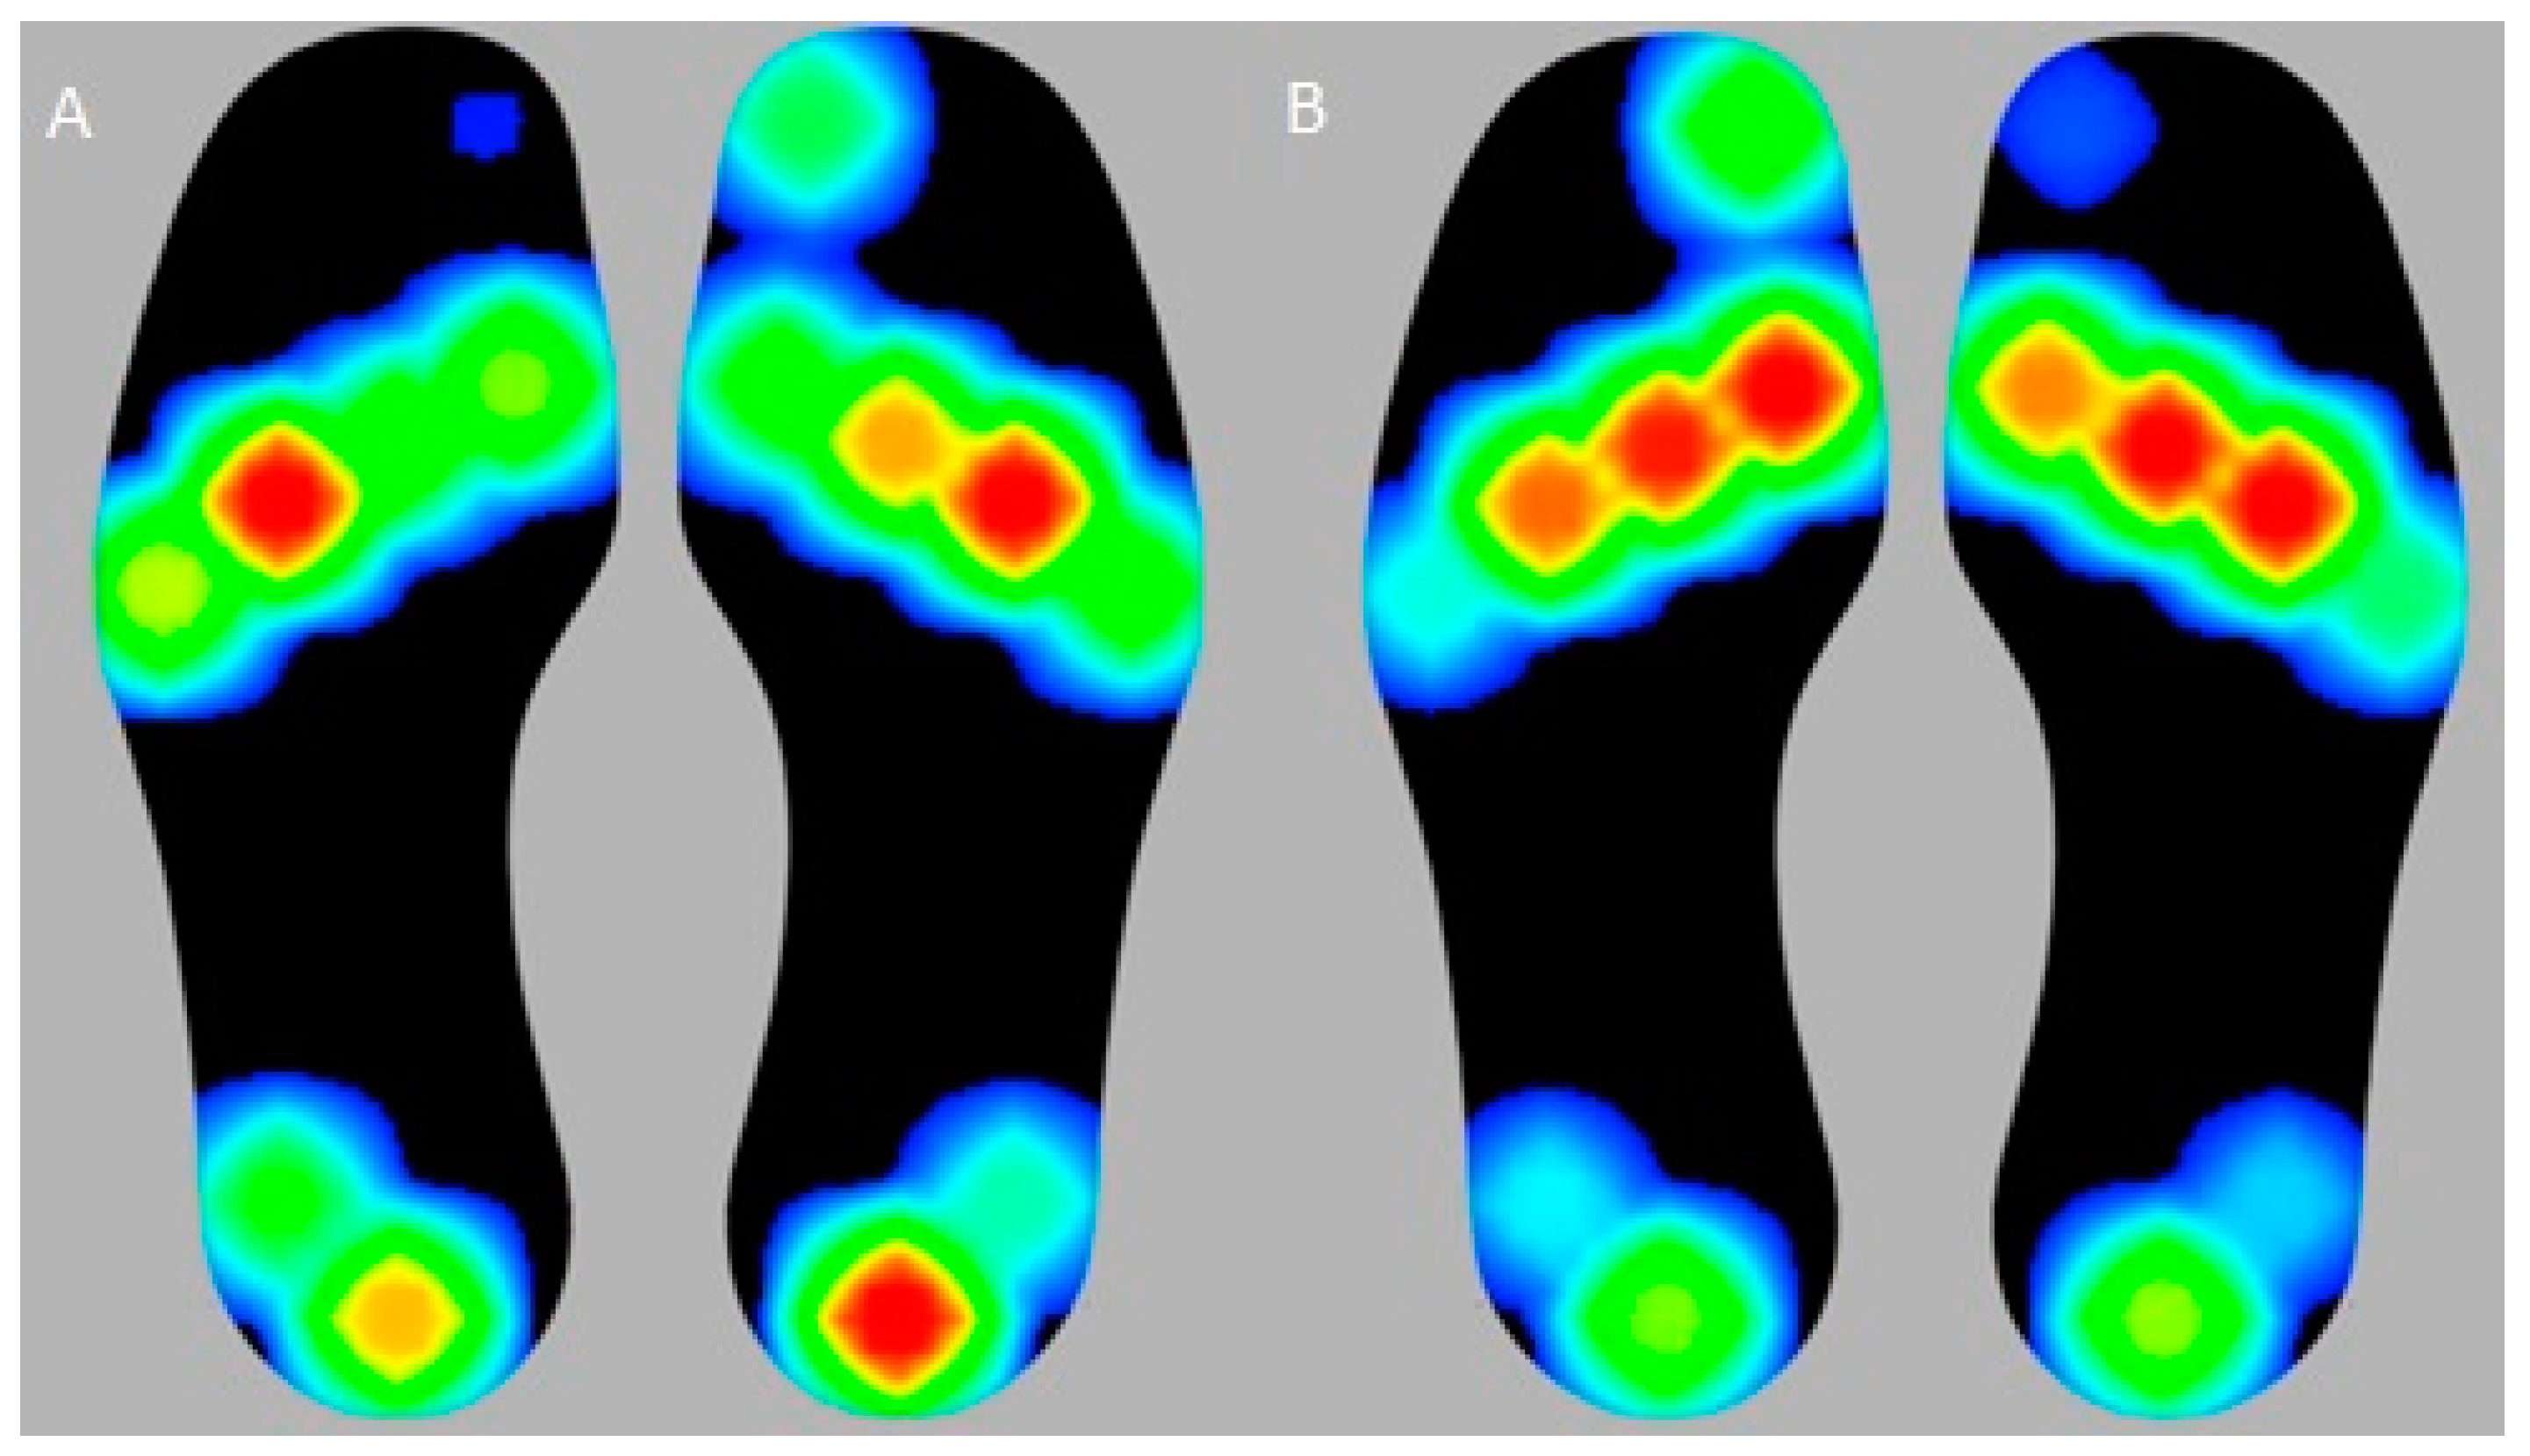

2.4. PP Measurement

3.3. Differences in Plantar Pressure Parameters before and after HV Surgery

| Peak-P | Baseline | Follow-Up (12 Months) | p-Value |

|---|---|---|---|

| Region 1 | 773.1 ± 663.5 (66.2–2148.2) | 1088.8 ± 236.7 (582.7–1545.5) | 0.027 * |

| Region 2 | 552.2 ± 256.7 (139.4–1290.5) | 844.1 ± 317.6 (260.8–1424.5) | 0.005 * |

| Region 3 | 714.71 ± 366.6 (118.5–1483.2) | 999.6 ± 383.1 (345.6–1858.1) | 0.024 * |

| Region 4 | 515.9 ± 402.8 (67.0–1586.1) | 631.7 ± 304.8 (31.7–1267.9) | 0.266 |

| Region 5 | 264.8 ± 316.0 (35.6–1419.3) | 415.7 ± 324.5 (0.5–1153.4) | 0.107 |

| Region 6 | 134.7 ± 166.5 (14.4–779.9) | 162.4 ± 128.8 (37.2–479.9) | 0.474 |

| Region 7 | 116.3 ± 195.7 (0.7–732.4) | 78.0 ± 121.8 (0.4–454.4) | 0.472 |

| Region 8 | 516.7 ± 274.3 (145.4–1293.2) | 528.9 ± 305.9 (13.0–1136.8) | 0.896 |

| Region 9 | 269.7 ± 280.9 (1.2–1158.2) | 228.6 ± 212.6 (1.2–926.5) | 0.394 |